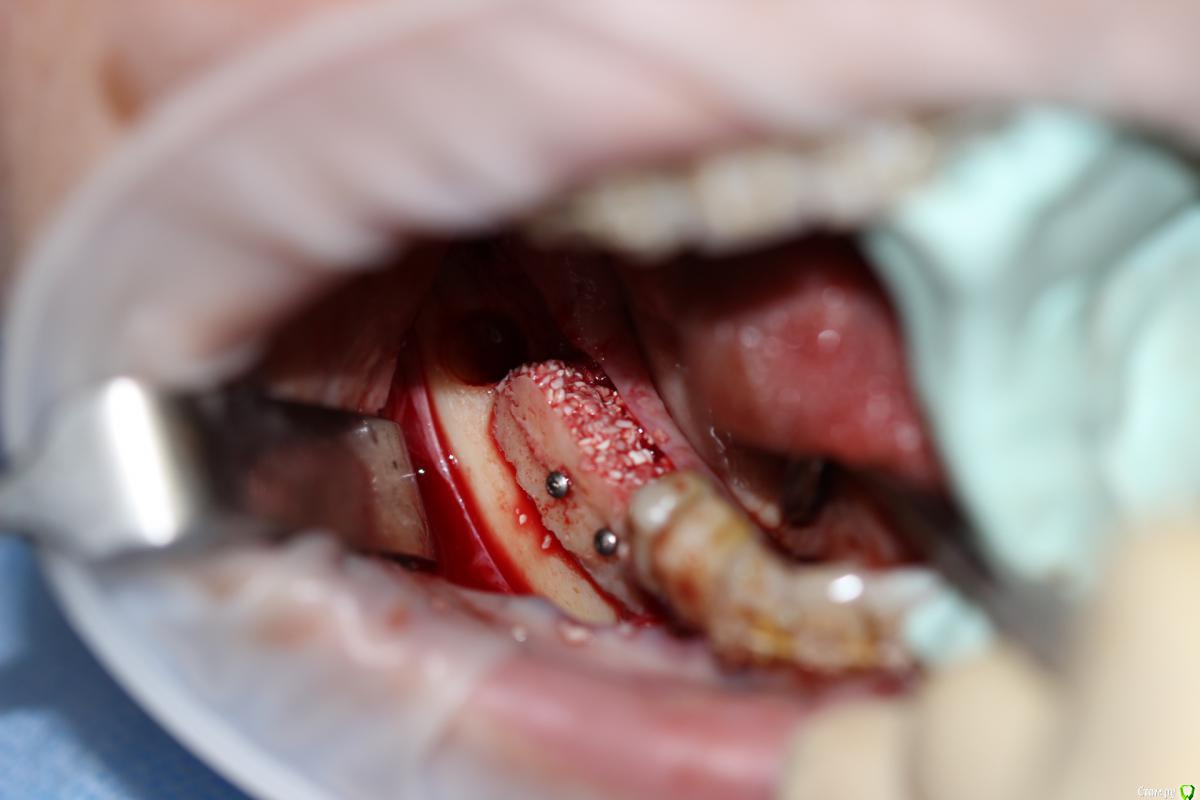

АнтонТЛТ Опубликовано 22 декабря, 2014 Поделиться Опубликовано 22 декабря, 2014 Название темы не соответствует выложенному кейсу. Тут не блоки, а ламинаты. И в классике нет графта, чистый ауто Ссылка на комментарий

Bier Опубликовано 22 декабря, 2014 Поделиться Опубликовано 22 декабря, 2014 в 3м, где вертикалили. Ссылка на комментарий

Bier Опубликовано 22 декабря, 2014 Поделиться Опубликовано 22 декабря, 2014 я бы в 3м сегменте пластику не стал бы делать. 1 Ссылка на комментарий

Чертков Александр Опубликовано 22 декабря, 2014 Поделиться Опубликовано 22 декабря, 2014 я бы в 3м сегменте пластику не стал бы делать.Олег, в 3м или всё таки в 4м? Ссылка на комментарий